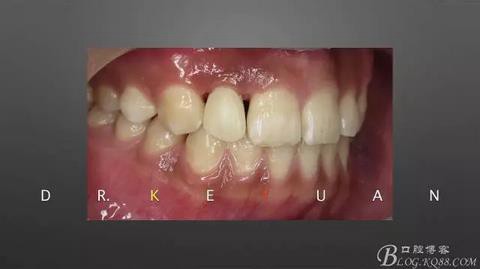

3、取硅橡膠模型制作氧化鋯樁

360截圖20170120135210335.jpg

4、粘接氧化鋯樁

360截圖20170120135217900.jpg